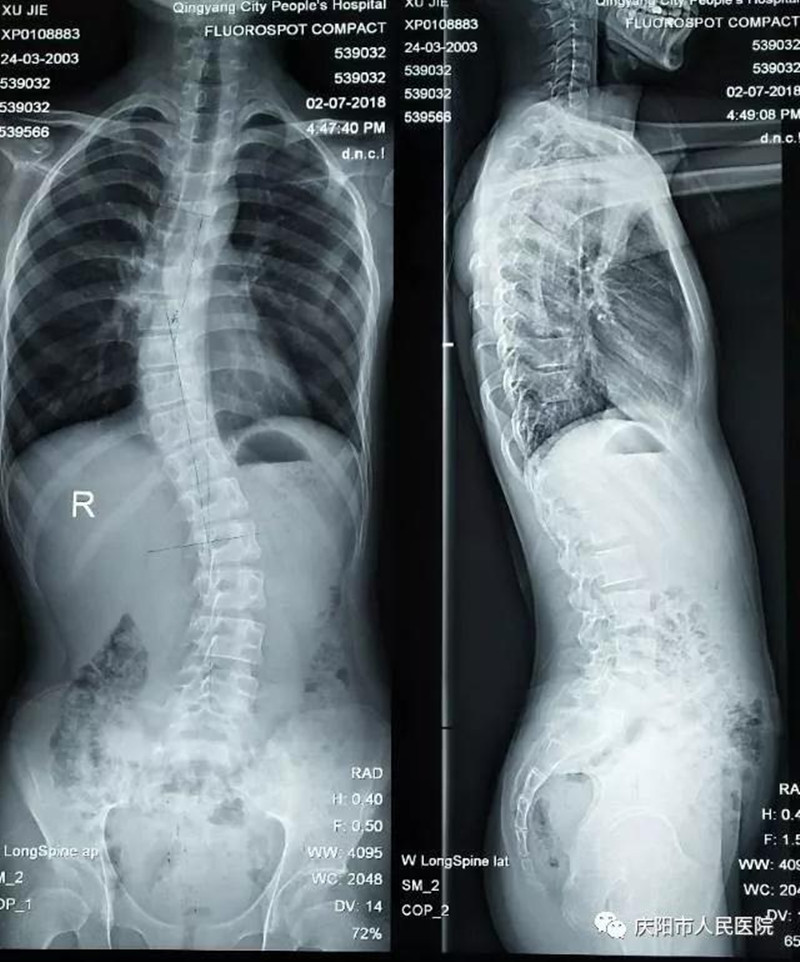

特发性脊柱侧凸畸形矫形手术成功实施。脊柱侧凸俗称脊柱侧弯,是一种脊柱的三维畸形,包括冠状位、矢状位和轴位上的序列异常,这是继脊柱后凸畸形矫形手术开展以来,我院骨一科在脊柱外科领域的又一项成就,标志着我院脊柱外科技术又向前迈进了一步。